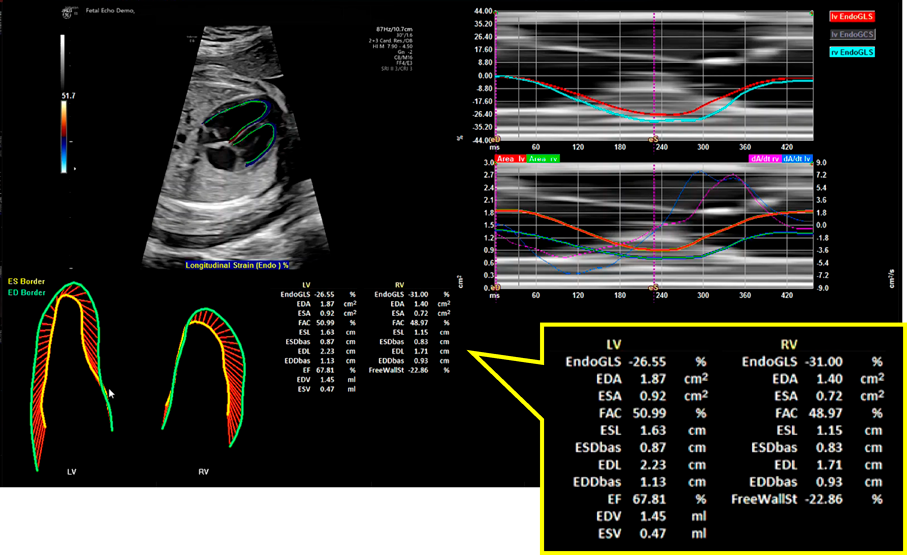

6. 新しい技術を使用した心機能評価

心エコー機器の技術的進歩により,Speckle tracking法を用いたストレイン計測や3D心エコーなどの新しい技術を用い,胎児でも心機能評価をより正確に行える可能性がある.ここではいずれも心電図を取得しなくても計測できる,Speckle tracking法による左右心室のストレイン計測とSpatio-Temporal Imaging Correlation(STIC)法により取得した4D画像を用いたEFの計測について示す.

6.1 Speckle tracking法による心室のストレイン計測

ストレインは初期長からの長さの変化率を示す指標で,初期長をL,初期長からの長さの変化をΔLとすると,ストレイン=ΔL/L(%)と表される.Speckle tracking法は,エコー画像上の小斑点(スペックル)をフレームごとにパターンマッチングして追跡することによって2点間のストレインを計測する方法である.Speckle tracking法によるストレインは画像の角度に依存せずに計測できる.ストレインは四腔断面像から計測される長軸方向のLongitudinal strain,短軸像から計測される円周方向のCircumferential strainと短軸方向のRadial strainの3方向の成分に分けて解析されるが,胎児では主にLongitudinal strainが計測されている.

ストレインは四腔断面像もしくは短軸像の画像を記録し,それをオフラインで解析して計測する.ストレイン解析を行う際には,記録した画像の画質が良好であることに加えて,胎児心拍数は140 bpm前後と速いために画像のフレームレートが十分に高いことが重要で,フレームレートが低いとストレイン値が不正確になる可能性がある.本来は心電図を基に1心周期を判定して計測されるが,胎児では心室壁の動きから1心周期を設定して解析が行われる.現在複数のメーカーの心エコー装置で胎児のストレイン計測が可能である(Fig. 7).ただし心エコー装置・解析ソフトウェアによって解析アルゴリズムが異なるため算出されるストレイン値も異なることに注意が必要である18).これまでに各メーカーの装置により計測された胎児心室のストレイン値が多数報告されているが,値や在胎週数による変化は報告により一定しない.本邦からも多施設共同研究による多数例の日本人正常胎児のストレイン値が報告されており,左室,右室のGlobal Longitudinal Strain; GLS(心室全体の長軸方向ストレイン)はそれぞれ−24.3±3.5%,−23.5±3.7%で,在胎週数が進むにつれて増加(絶対値は低下)するとされている19)

Pediatric Cardiology and Cardiac Surgery 41(1): 11-19 (2025)

Fig. 7 Speckle tracking法を用いた胎児左室・右室のストレイン解析結果画面

データを拡大して示す.